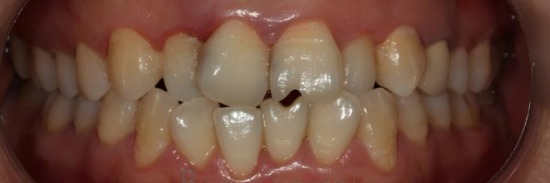

暫定美的臨床症例

手術前のビュー妥協した歯の構造と美学を示しています。